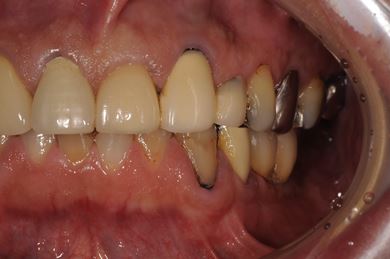

治療前

• 治療前